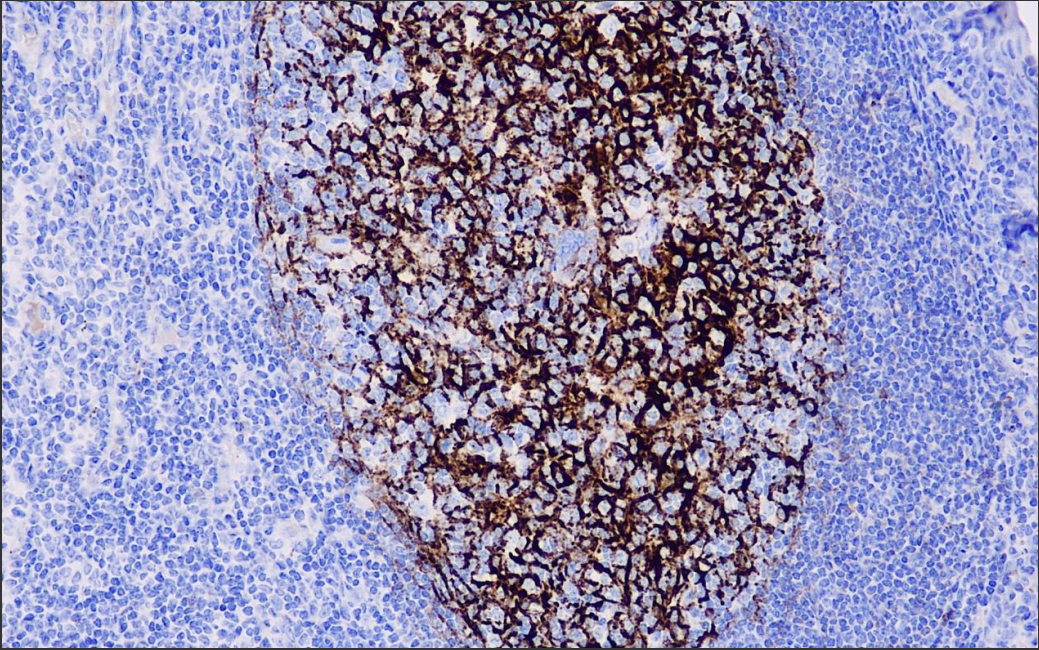

Positive control: tonsils/acute kidney transplant rejection

C4d is a stable split product of classical complement activation and can be used to detect chronic kidney transplant rejection as well as hyperacute rejection, acute vascular rejection, acute cellular rejection, and borderline rejection. In these rejection reactions, C4d is deposited in the peritubular capillaries of the kidney.C4d assay can be used as an important indicator of renal graft survival and treatment of acute rejection.

C4d Antibody Reagent binds specifically to C4d molecular antigen. Immunohistochemistry kits containing C4d Antibody Reagent are suitable for precise diagnosis of transplant rejection and autoimmune diseases.